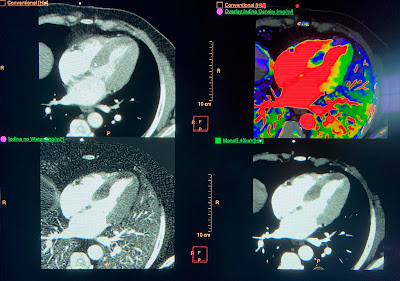

Вверху слева: обычная КТ.

Вверху справа - раскрашено наложением иода; Синие участки миокарда - это ишемия.

Внизу слева - простая картирование йодом.

Внизу справа - изображение с низким значением киловольт-электронов, которое излучает йод. Обратите внимание на 2 очень темные области, одну в перегородке, а другую возле верхушки. Обратите внимание, что они коррелируют с синим цветом на цветном спектральном КТ (синий - ишемия на спектральном КТ).

Эти области гипоперфузии находятся в перегородке и верхушке, что указывает на ишемию ПМЖВ. Кроме того, они действительно трансмуральные!

Сравните трансмуральную ишемию КТ с субэндокардиальной ишемией КТ (Изображение субэндокардиальной ишемии)

Ниже мы видим корональное (фронтальное) изображение сердца:

Обратите внимание, что нижняя стенка (нижняя часть изображения) слегка трансмурально темнее, чем остальная часть.

По словам нашего компьютерного гуру, Гопала Пенджаби (https://twitter.com/CtSpectral), если проспективно интерпретировать вслепую, это не является окончательной диагностикой.

Это предполагает наличие нижнего ИМО, но ни в коем случае не является диагностическим.